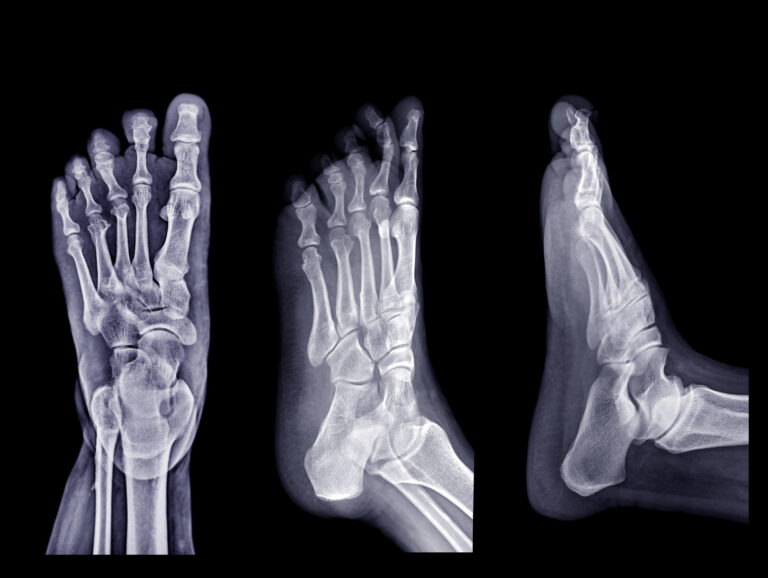

Marc Darrow, MD, JD. Midtarsal joint sprains are caused by ligament injuries that are responsible for holding the rear and mid-sections of the foot together. Injuries to these ligaments will cause pain, swelling, and obvious bruising in the middle or top of the foot Treatment typically involves the RICE method (Rest, Ice, Compression, and Elevation), … Continue reading Treating mid-tarsal – transverse tarsal joint sprains | Joint Rehab Los Angeles